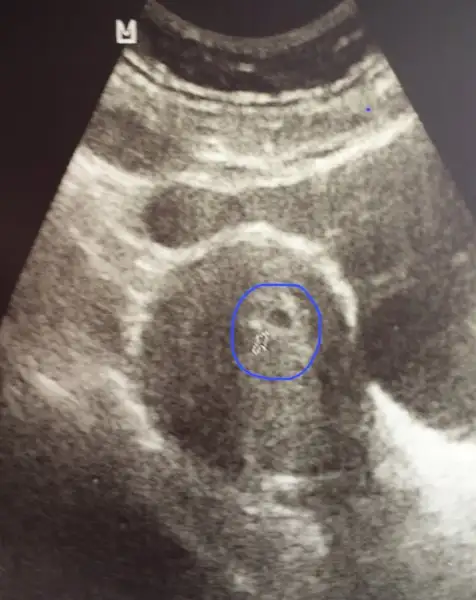

Evet minik bir kese gorundu

Embriyo henüz görünmüyor

Ama genetik bir sorun olma ihtimaline karşı henüz sevinemedik.. yaşımdan dolayı..

kalp atışını duyarsak insallah biraz daha rahatliycaz sanırım

Şimdilik bir kesemiz var buna da şükür